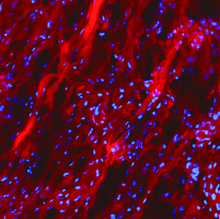

CHP is a powerful histopathology tool which enables straightforward detection of inflammation and tissue damage caused by a large variety of diseases, as well as tissue remodeling during development and aging. CHP robustly visualizes the pericellular matrix turnover caused by proteolytic migration of cancer cells within 3D collagen culture, without the use of synthetic fluorogenic matrices or genetically modified cells. CHP can measure and localize mechanical injury to collagenous tissue at the molecular level. It also enables assessment of collagen denaturation in decellularized extracellular matrix. In addition, CHP can be used to specifically visualize collagen bands in SDS-PAGE gels without the need for western blot.

- Cell invasion - reveal collagen turnover: Gain direct evidence of protease mechanisms by imaging degraded collagen in complex 3D settings. This robust method bypasses synthetic hydrogels and genetic modification, overcoming key assay limitations. Such clarity is vital for understanding cancer metastasis and finding new therapies against invasive diseases. More on cell invasion...

Histopathology - unlock new insights in tissue damage: CHPs precisely detect and quantify denatured collagen, a hallmark of disease. CHPs are applicable to nearly all tissue types and a wide range of medical areas. More on histopathology...